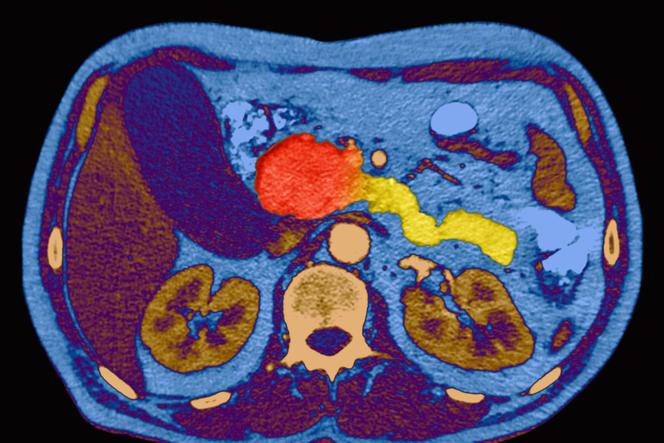

Tumor da cabeça do pâncreas visível no centro da imagem, em vermelho, em tomografia computadorizada colorida de abdome em corte axial.